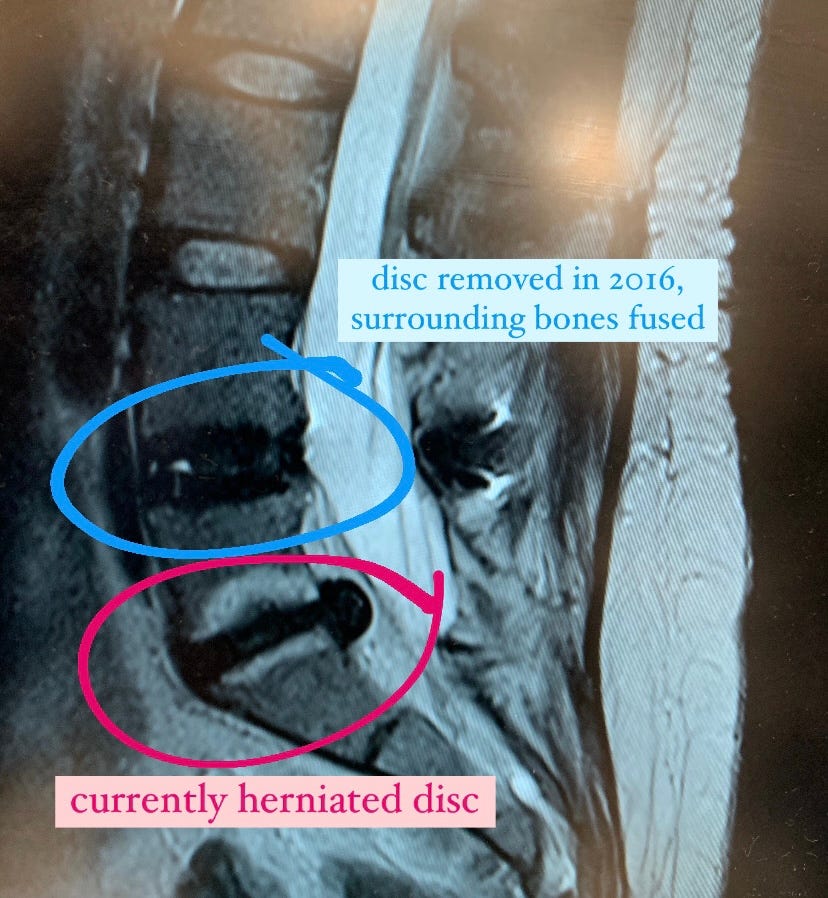

My discs, the bouncy bits in between my spine bones, are prone to slippage. It happened to me at 17 for the first time really intensely and caused something called Cauda Equina Syndrome. (Google it! It still grosses me out to explain.) In 2018 I was moments away from being paralyzed from the waist down and needed emergency spinal fusion surgery. My surgeon at that time said I had the spine of an 80 year old, so I guess that means I’m super mature for my age.

As a result of various levels of injury, my ability has fluctuated wildly in the past 10 years. I hurt myself at a callback about 5 months ago which put me in a place where I can only stand, sit, or lay down for 40ish minutes without being in pain. As a result I wake up every morning around a 7 on the pain scale. When I sneeze I often pee myself (only a little!) I can’t bear more than 10 lbs of weight, and generally my nervous system is a little wacky. My extremities fall asleep easily because my nerves get pinched. I had my fusion at L4/L5 so I lost a few levels of movement in my lower back. It’s very much giving that fish from the SpongeBob chocolate bar episode.